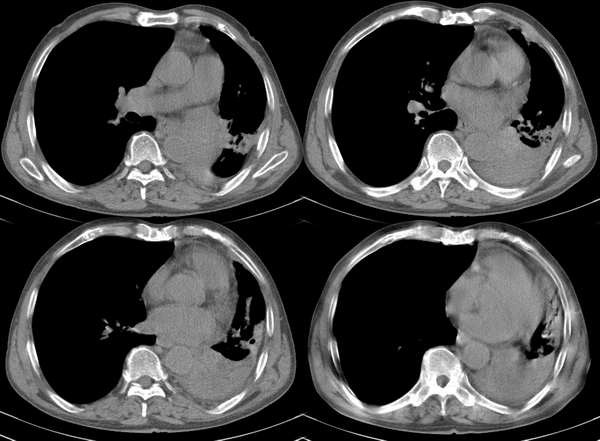

m67y外院ct诊断肺ca,现来我科复查ct

左肺下叶支气管狭窄局部见肿块影左肺下叶不张,肺癌应该没问题吧

典型中央型肺ca

左主支气管变窄,左下叶部分不张,考虑肺癌可能性大

考虑左下肺中央型肺癌并肺不张,建议支气管镜检查。

主-肺动脉窗似有大的淋巴结,肝也像有多发低密度灶。看不太清,是不是转移?